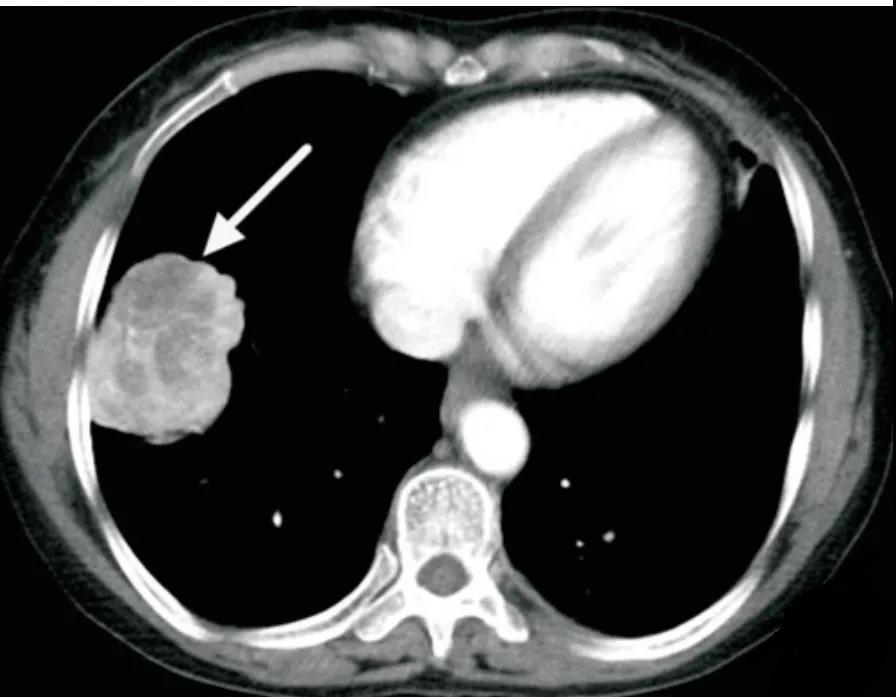

硬化性肺细胞瘤

多为单发孤立病灶,偶有多发,病灶呈圆形或类圆形,边缘清楚,密度均匀,多无毛刺,可见浅分叶,部分可见钙化、囊性变。

增强扫描病灶强化方式及程度与肿瘤成分及微血管数量相关,可表现为均匀显著强化,或不均匀轻度强化

可见特征性血管贴边征(图 2)和周围血管包绕征,即增强动脉期见病灶边缘明显强化的点状血管断面

可伴特征性尾征(图 3),即占位边缘的尾状突起,多位于近端靠近肺门一侧

另可见特征性空气新月征,上述可帮助与其他良性肿瘤及肺癌鉴别